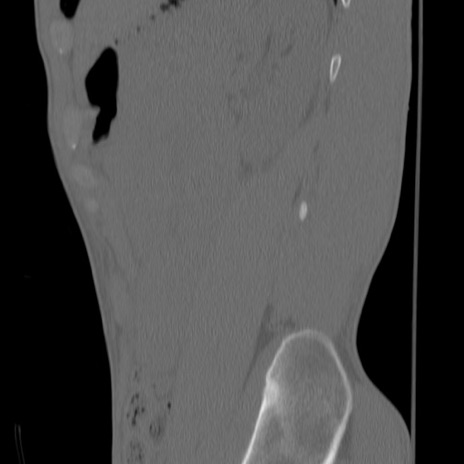

症例3 腰椎CT(矢状断像)

【症例】30歳代男性

【主訴】腰痛

【現病歴】本日旅行先で観光中に、友人と衝突し転倒し受傷。

【身体所見】麻痺なし、右下腿内側前面外側、左下腿内側に知覚鈍麻・しびれ

異常所見と診断は?

腰椎CT